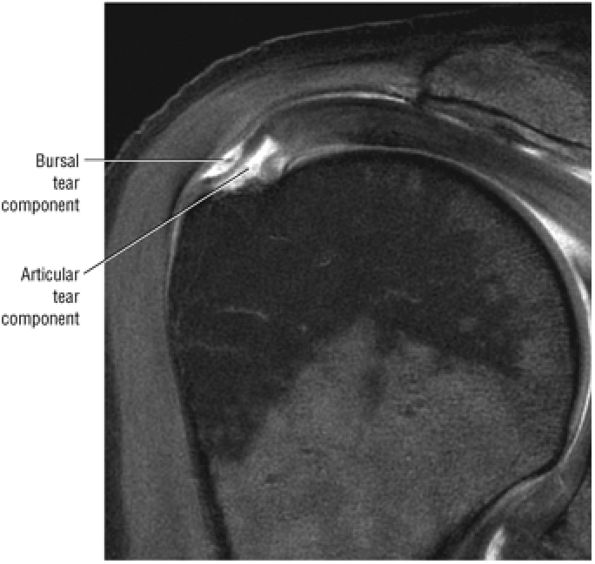

FIGURE 8.102 ● (A) The anterior undersurface of the acromion and the coracoacromial ligament form the coracoacromial arch. The subacromial subdeltoid bursa facilitates the passage of the rotator cuff and proximal humerus under the coracoacromial arch. (B) A superior axial image shows the anterior-to-posterior extent of the coracoacromial (CA) ligament perpendicular to the supraspinatus tendon. The fluid in the subacromial-subdeltoid bursa represents fluid between two serosal surfaces in contact with each other. One serosal surface is contributed by the undersurface of the coracoacromial arch and deltoid, and the other serosal surface is on the bursal side of the cuff.

|

![]() |